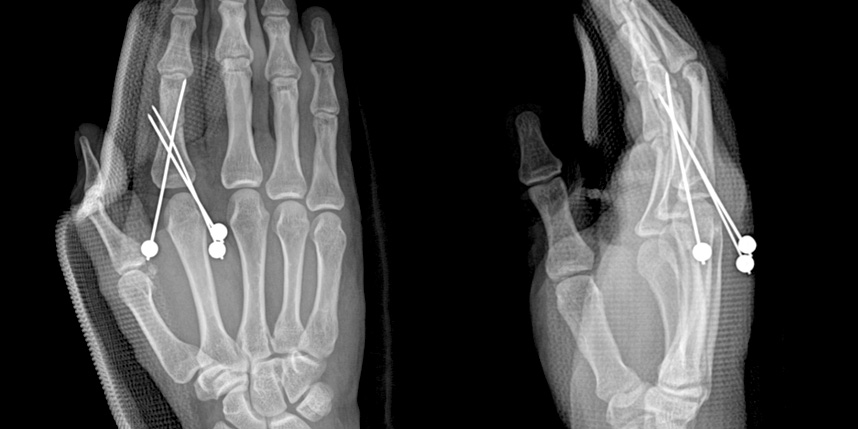

손가락 골절

골절이 심하지 않은 경우에는 깁스로 고정해서 유합을 시킬 수 있으나, 정도가 심한 경우에는 손,발목 골절 수술을 진행할 수 있습니다.

골절은 정확하게 골절편을 잘 맞추고 고정하는 것이 중요합니다. 특히 관절면을 잘 맞추는 것이 중요합니다.